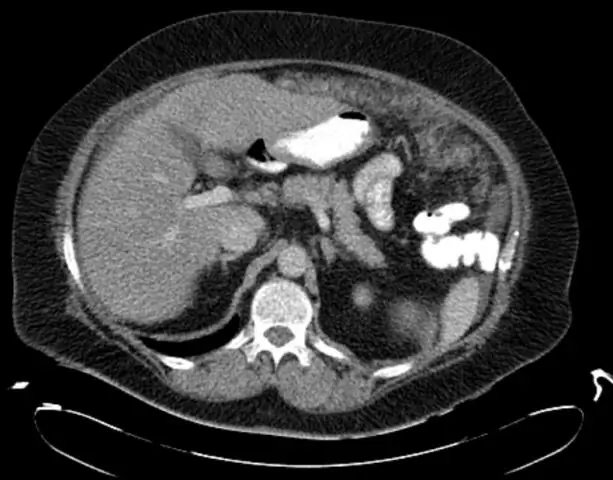

Первоначальный диагноз инсульта головного мозга был рассмотрен, поэтому дипиридамол и аторвастатин были добавлены к его лекарству через четыре дня после его поступления в нашу больницу. Между тем, компьютерная томография (КТ) мозга показала, что у него не было явного инфаркта.

Показания КК снизились за этот период и вернулись к нормальным уровням через неделю после прекращения приема статинов (рис. 1).

фигура 1

Это изображение графика показывает показания креатининкиназы при поступлении и корреляцию с клиническим прогрессом.